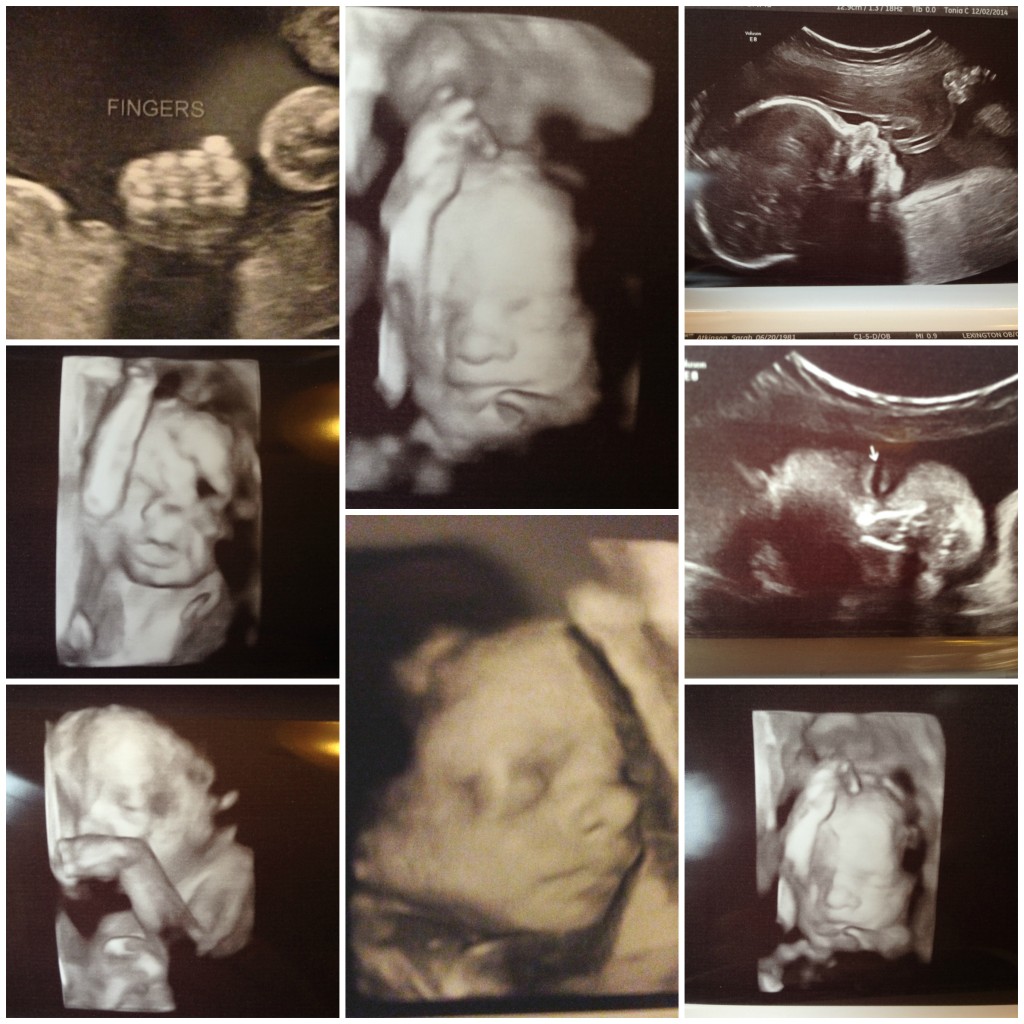

You’ve been such a trouble maker this past month! My contractions continued since our last update, which resulted in several more visits to the OB to ensure you would stay baking in my belly instead of making an early appearance. With each appointment, they used the ultrasound to make sure that the contractions weren’t changing my cervix. I’m pleased to report that you just like getting into mischief, and are still happy, healthy and growing. Each time they did an ultrasound, we got to see your sweet little face again! We even saw you open your eyes- twice!! The technician was really excited to see you opening and closing your eyes because apparently that’s pretty rare to catch on ultrasound. We saw you moving your arms and legs around and opening your mouth as well. Your legs are measuring long, taking after Daddy already!